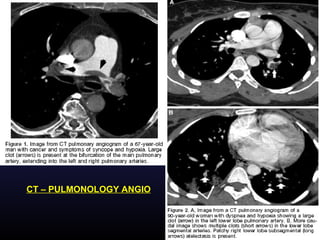

CT – PULMONOLOGY ANGIO

• In patients with strong clinical suspicion, the initial

investigation of choice is spiral CT pulmonary

angiography. D-DIMER is a negative predictive value (‘rule